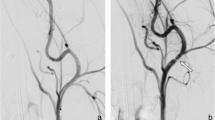

An alternative strategy is the use of a flow diverting stent, i.e. a bare stent with high strut density. In cerebral aneurysms, flow diverters effectively reduce flow in the aneurysm and promote aneurysm thrombosis and subsequent shrinkage [4]. PAA can be treated in this fashion using the Supera interwoven nitinol stent [5] (Abbott, Santa Clara, CA). During deployment, the stent can be locally compressed to achieve a high mesh density (Fig. 1; Video 1), creating a flow diverting configuration that can be augmented by using multiple Supera stents. In two PAA cohorts treated with 1–3 Supera stent layers, the 1-year patency was 85–100% and at median 44-month follow-up, patency was 67% [5, 6]. Aneurysm thrombosis was seen in 88% within a week, and in 100% through 4-month follow-up [5]. Potential advantages include increased flexibility with respect to diameter transitions and patency of overstented side-branches.

Two pilot studies investigated the off-label use of the Supera stent as a flow diverting configuration in patients. The first study [5] used a dual-lined Supera stent in 28 out of 31 cases and reported aneurysm thrombosis in all of them at 4-month follow-up, whereas the second [6] used a dual-lined Supera stent in 10 out of 28 cases with an aneurysm thrombosis rate of 34.5% at 12-months, both under dual-antiplatelet therapy for the first postoperative months. Both studies deployed the Supera stent with maximal compression, which maximizes the flow modulating effect and additionally benefits stent patency [17]. Whether the incidence of aneurysm thrombosis in the dual-lined vs single-lined group was higher in the second study was not reported. Although inconclusive, these results suggest that the improved hemodynamics of a dual-lined Supera stent observed in our in-vitro measurements are relevant in-vivo and may lead to improved aneurysm thrombosis rates. However, other factors, including a higher incidence of backflow, may also contribute to the difference in aneurysm thrombosis.